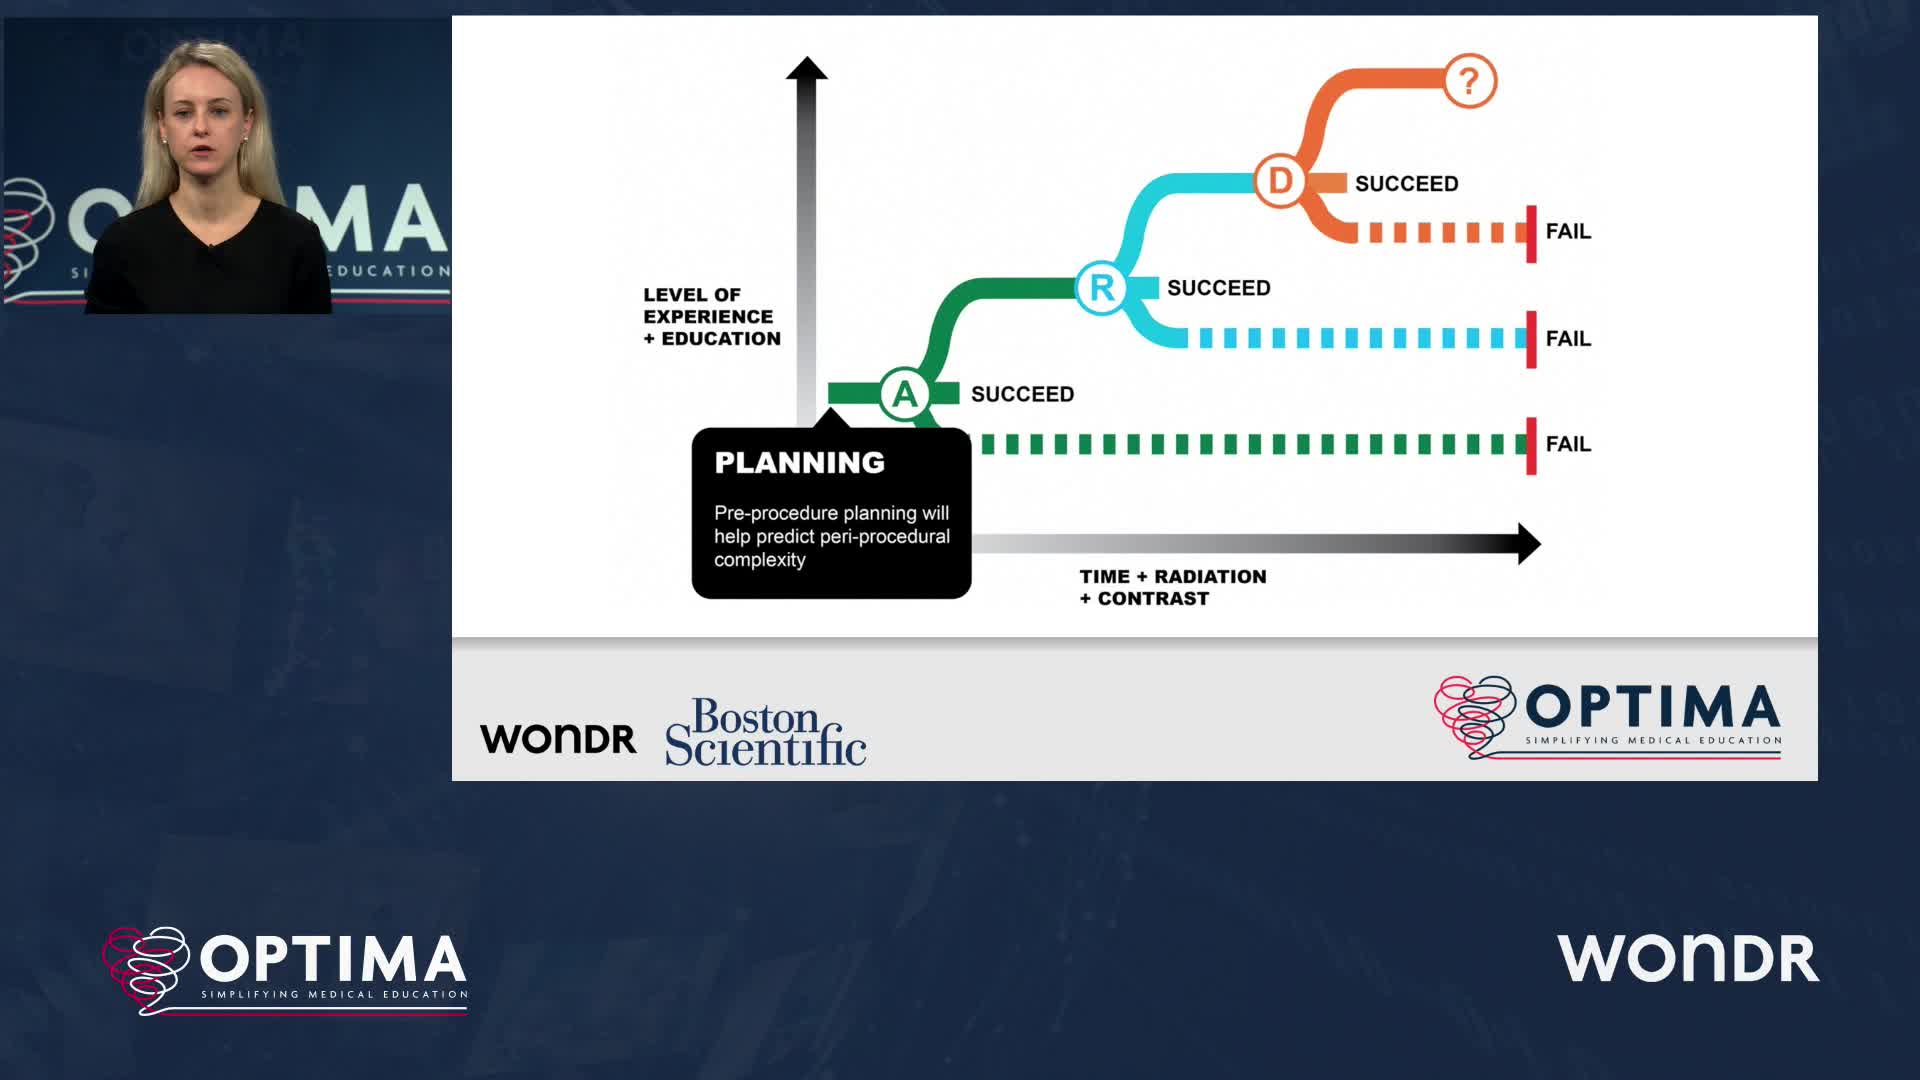

Session 1: Pre-procedure planning – are we lost without a map?